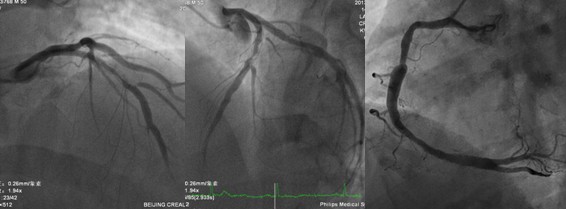

入院后择期行冠状动脉造影(图1)。

支架内出现狭窄,考虑到反复出现支架内狭窄,建议外科治疗,在与患者及家属沟通后选择介入治疗。选择6F的EBU3.5指引导管,应用runthrough指引导丝到达病变远端后应用2.5x15mm的球囊以12atm扩张,重复造影显示前降支血流消失(图2)。

图2 前降支中段后无血流,回旋支正常显影